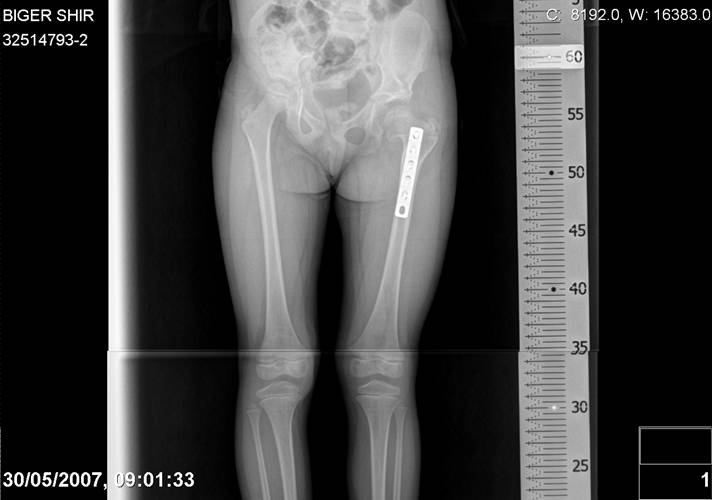

[Ortho] Врожденный вывих бедра

Navernoe Dega

Chto by ne byt goloslovnym posilau vam svoi sluchai gde sdelal vse chto napisal vyshe